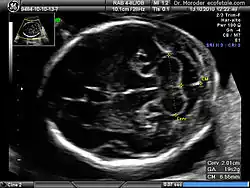

Congenital malformation, hereditary disorders, and acquired conditions can affect cerebellar structure and, consequently, cerebellar function. Unless the causative condition is reversible, the only possible treatment is to help people live with their problems.[67] Visualization of the fetal cerebellum by ultrasound scan at 18 to 20 weeks of pregnancy can be used to screen for fetal neural tube defects with a sensitivity rate of up to 99%.[68]